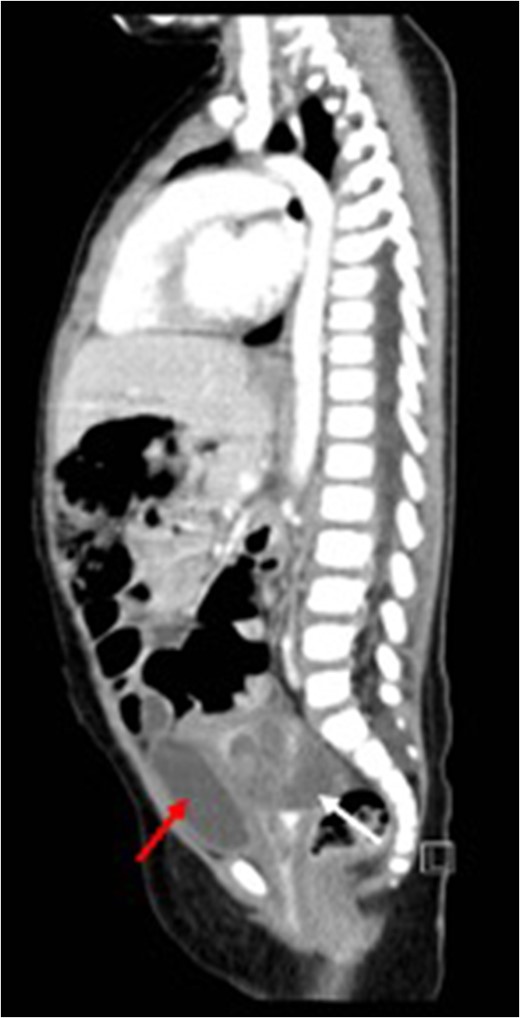

Sagittal view (CT) for the mass (white arrow) post-chemotherapy showing reduction in size (red arrow) bladder.